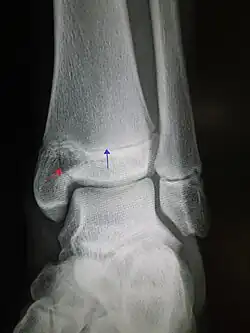

| An X-ray of the left ankle showing a Salter–Harris type III fracture of medial malleolus. Red arrow demonstrates fracture line while the blue arrow marks the growth plate. | |